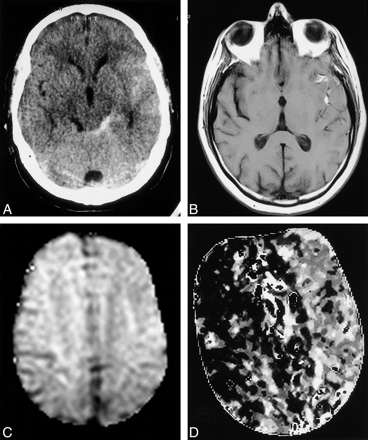

Images in patient 22, 6 d after SAH.

A, Hemorrhage is visible on this CT scan of the left sylvian fissure and perimesencephalic cisterns.

B, Spin-echo T1-weighted (501/16 [TR/TE[) MR image shows a high-signal-intensity change, due to T1 shortening, in the hemorrhage.

C, Diffusion-weighted image shows no abnormality.

D, Cerebral perfusion is reduced, as shown by increased time to peak in the left hemisphere on this map.